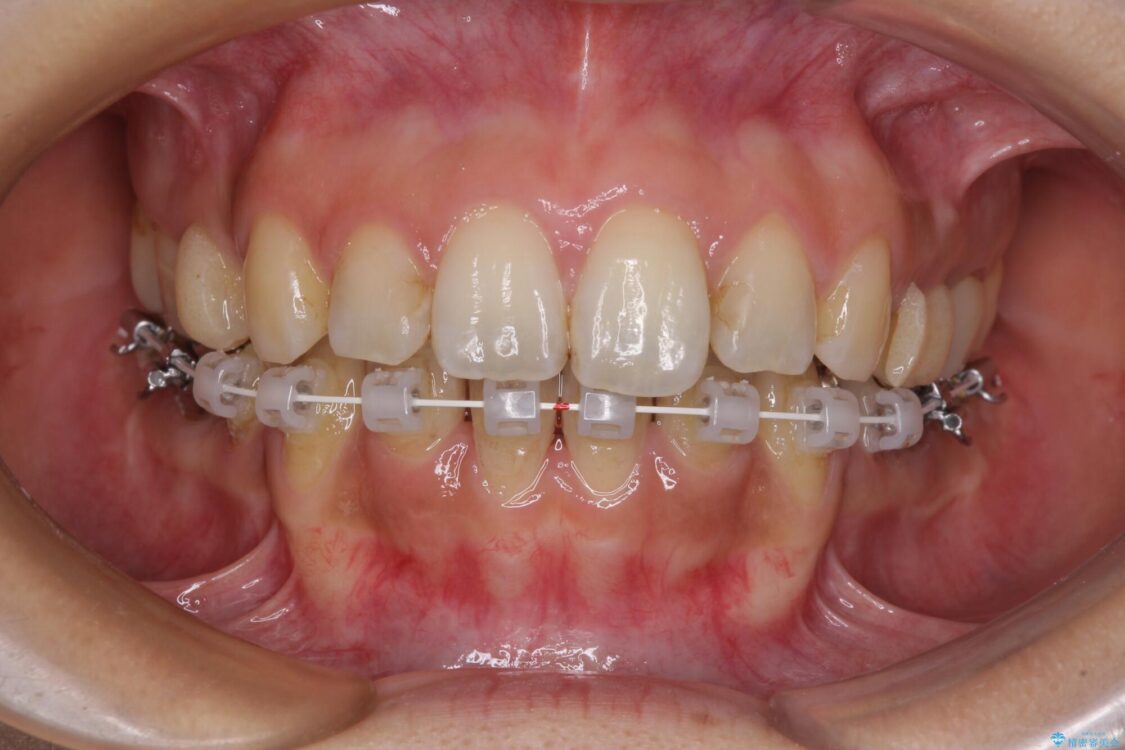

前歯のデコボコと上顎の前突感による口の閉じにくさを気にして来院された患者様です。

目立たない装置を希望されたので、上顎が裏側装置のハーフリンガルを選択し、上下左右の小臼歯(計4歯)を抜歯して矯正治療を行うこととしました。

治療途中

• デコボコと口元の突出感 ハーフリンガルでの抜歯矯正 治療途中画像